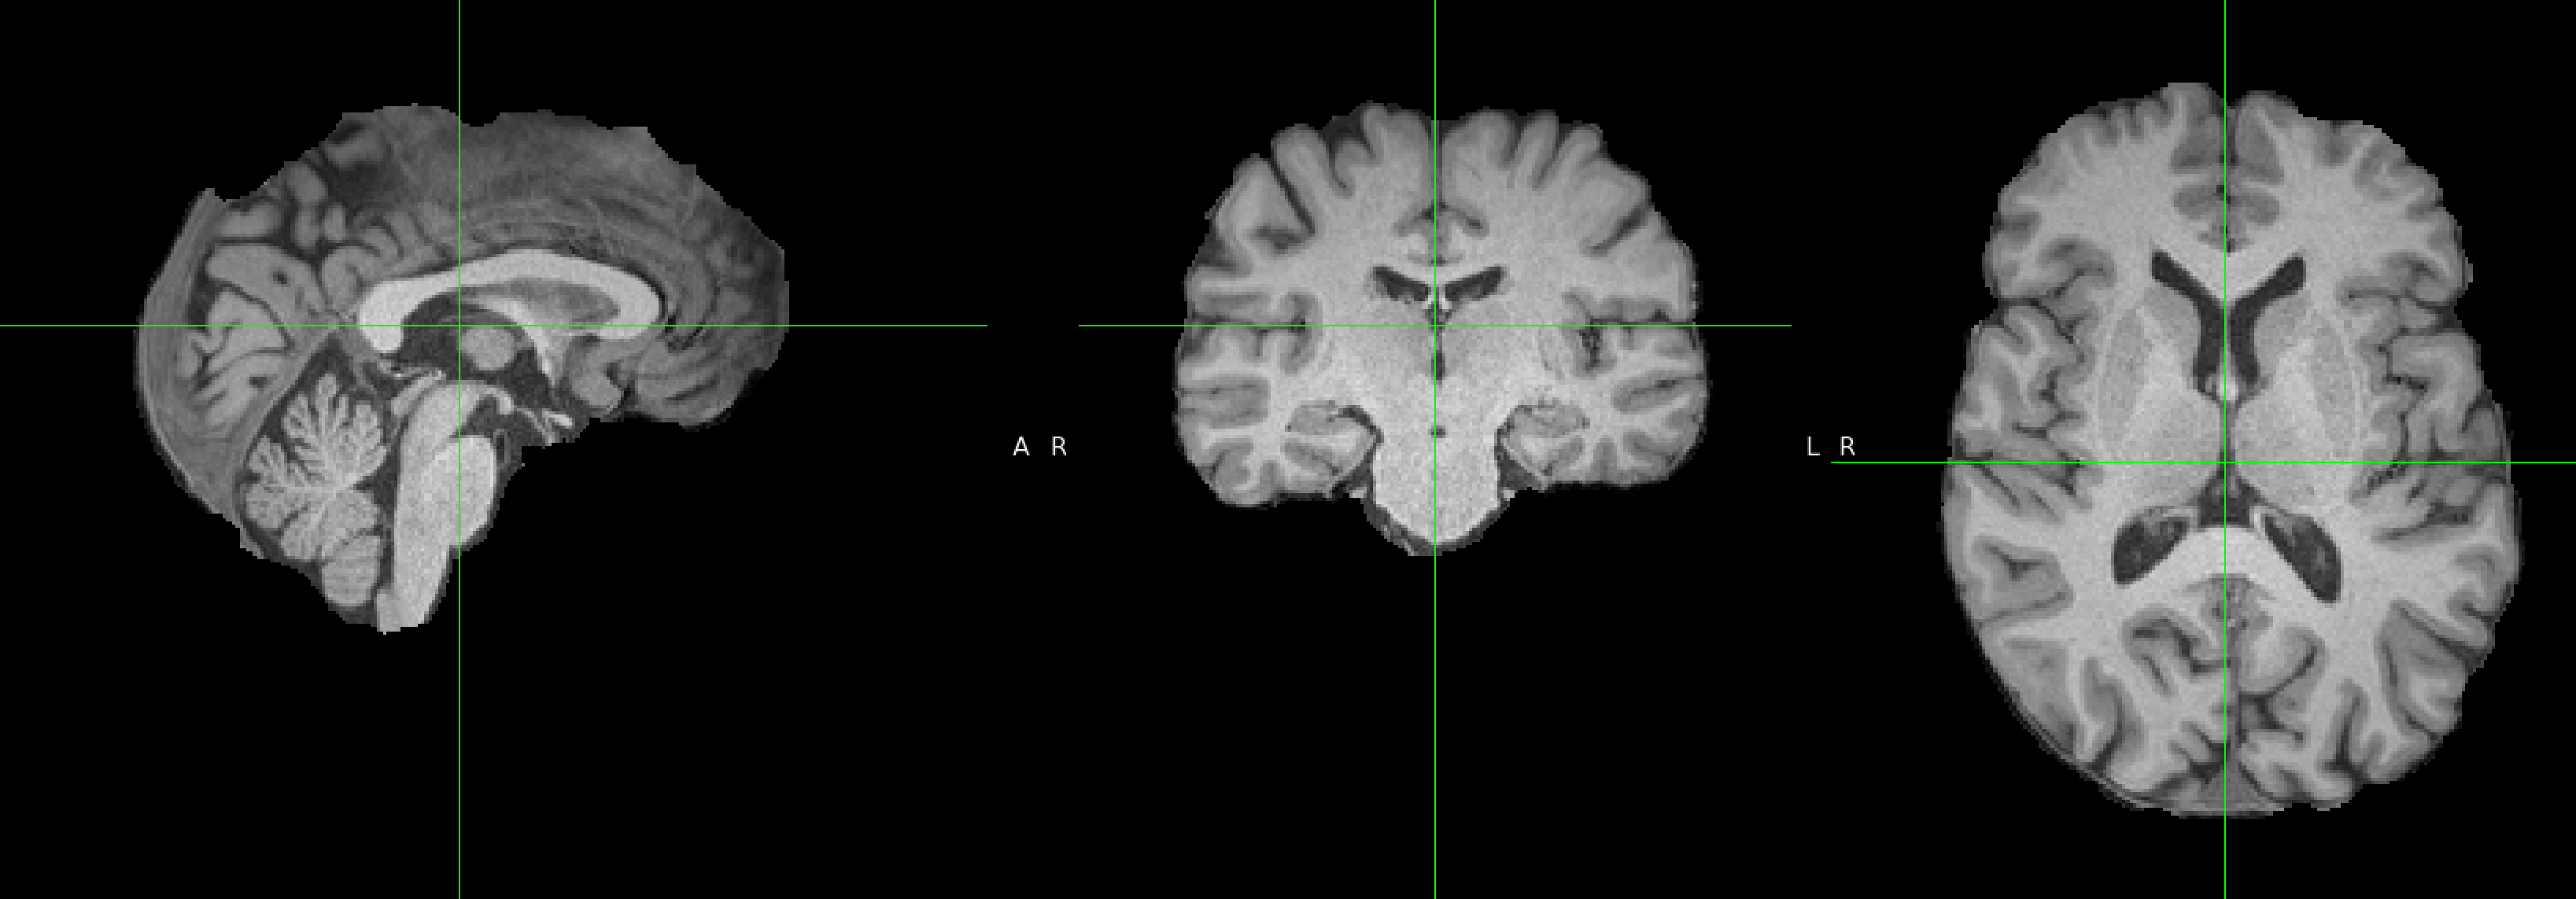

请问一下老师,在做FSL-VBM的时候,先用fslvbm_1_bet -N做脑提取,结果保留了一些脑膜,这会影响后续分析吗?

脑提取总是不完美的,图中这种情况应该是可以接受的。另外,我也推荐你试试FreeSurfer里的mri_synthstrip,我个人觉得脑提取比FSL的BET要更准确更稳健。